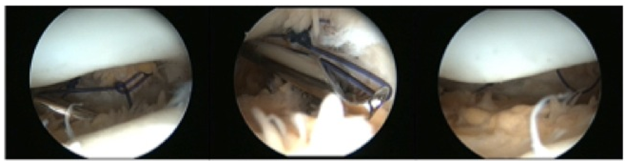

Knee radiograph evaluation (Figure 1 & 2) demonstrated a trochlear groove angle > 145º and type III patella according to the Wiberg classification as well as a crossing sign; there were no arthritic changes and no patella alta or baja; CT scan (Figure 3) showed femoral trochlea dysplasia, normal TT-TG, patella external translation and patella chondromalacia; MRI had the same findings as the CT and reported normal menisci and ligaments.

Figure 1 45º x-ray patellofemoral view (Merchant view) demonstrating trochlear groove angle > 145º and type III patella according to the Wiberg classification.

Figure 4 Intra operative arthroscopic images showing the suture limbs being passed in the medial retinaculum over the Tuohy needle, and the final aspect before knot tying, after the synovial abrasion between suture limbs

Figure 5 Intra operative arthroscopic images showing knot tying and the final image after the medial retinaculum plication.